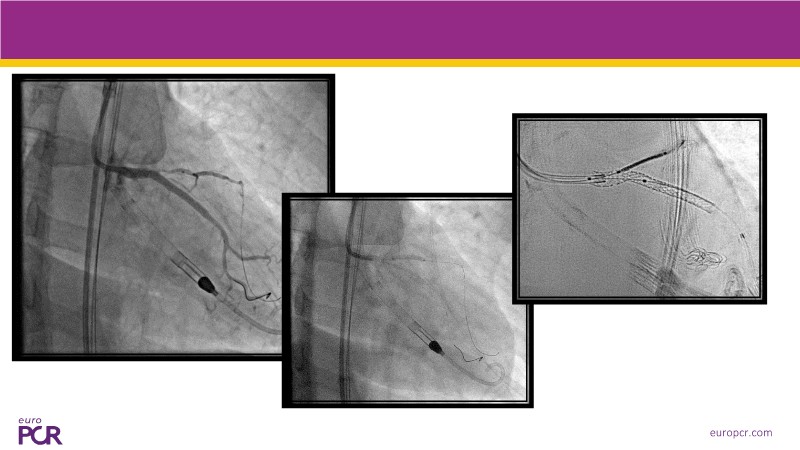

This EuroPCR 2025 session offers a comprehensive update on cardiogenic shock and high-risk PCI, featuring expert analysis of the DanGer-SHOCK and ECLS-SHOCK trials, new insights one year after DanGer-SHOCK, and practical considerations for managing PCI in patients with severely reduced LVEF. Expect to gain a deeper understanding of mechanical support strategies, survival optimisation, and the latest consensus on treating patients unsuitable for surgery.

- To learn the latest data on Impella in cardiogenic shock